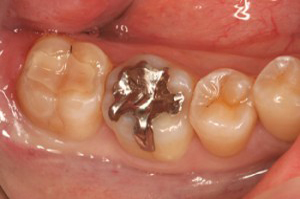

■口の中の金属を白くする症例

セット後